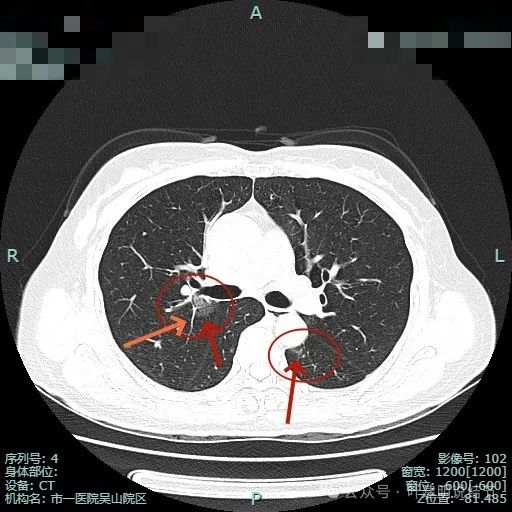

左下叶背段病灶出现(病灶1),靠叶间裂,密度不纯,若单此层当然并不一定是恶性,也可能是慢性炎的。

胸膜似略有牵拉密度不纯。

出现小空泡征以及偏实性成分,并有淡磨玻璃成分,整体轮廓较清,瘤肺边界较为清楚。

叶间胸膜有牵拉,病灶内部密度欠均匀。表面有浅分叶征。

右上主病灶出现(病灶2),离肺门部非常近,密度较淡。

病灶1有明显叶间裂牵拉影响;病灶2密度虽淡,但轮廓清,贴着支气管壁。也有小血管走向病灶。